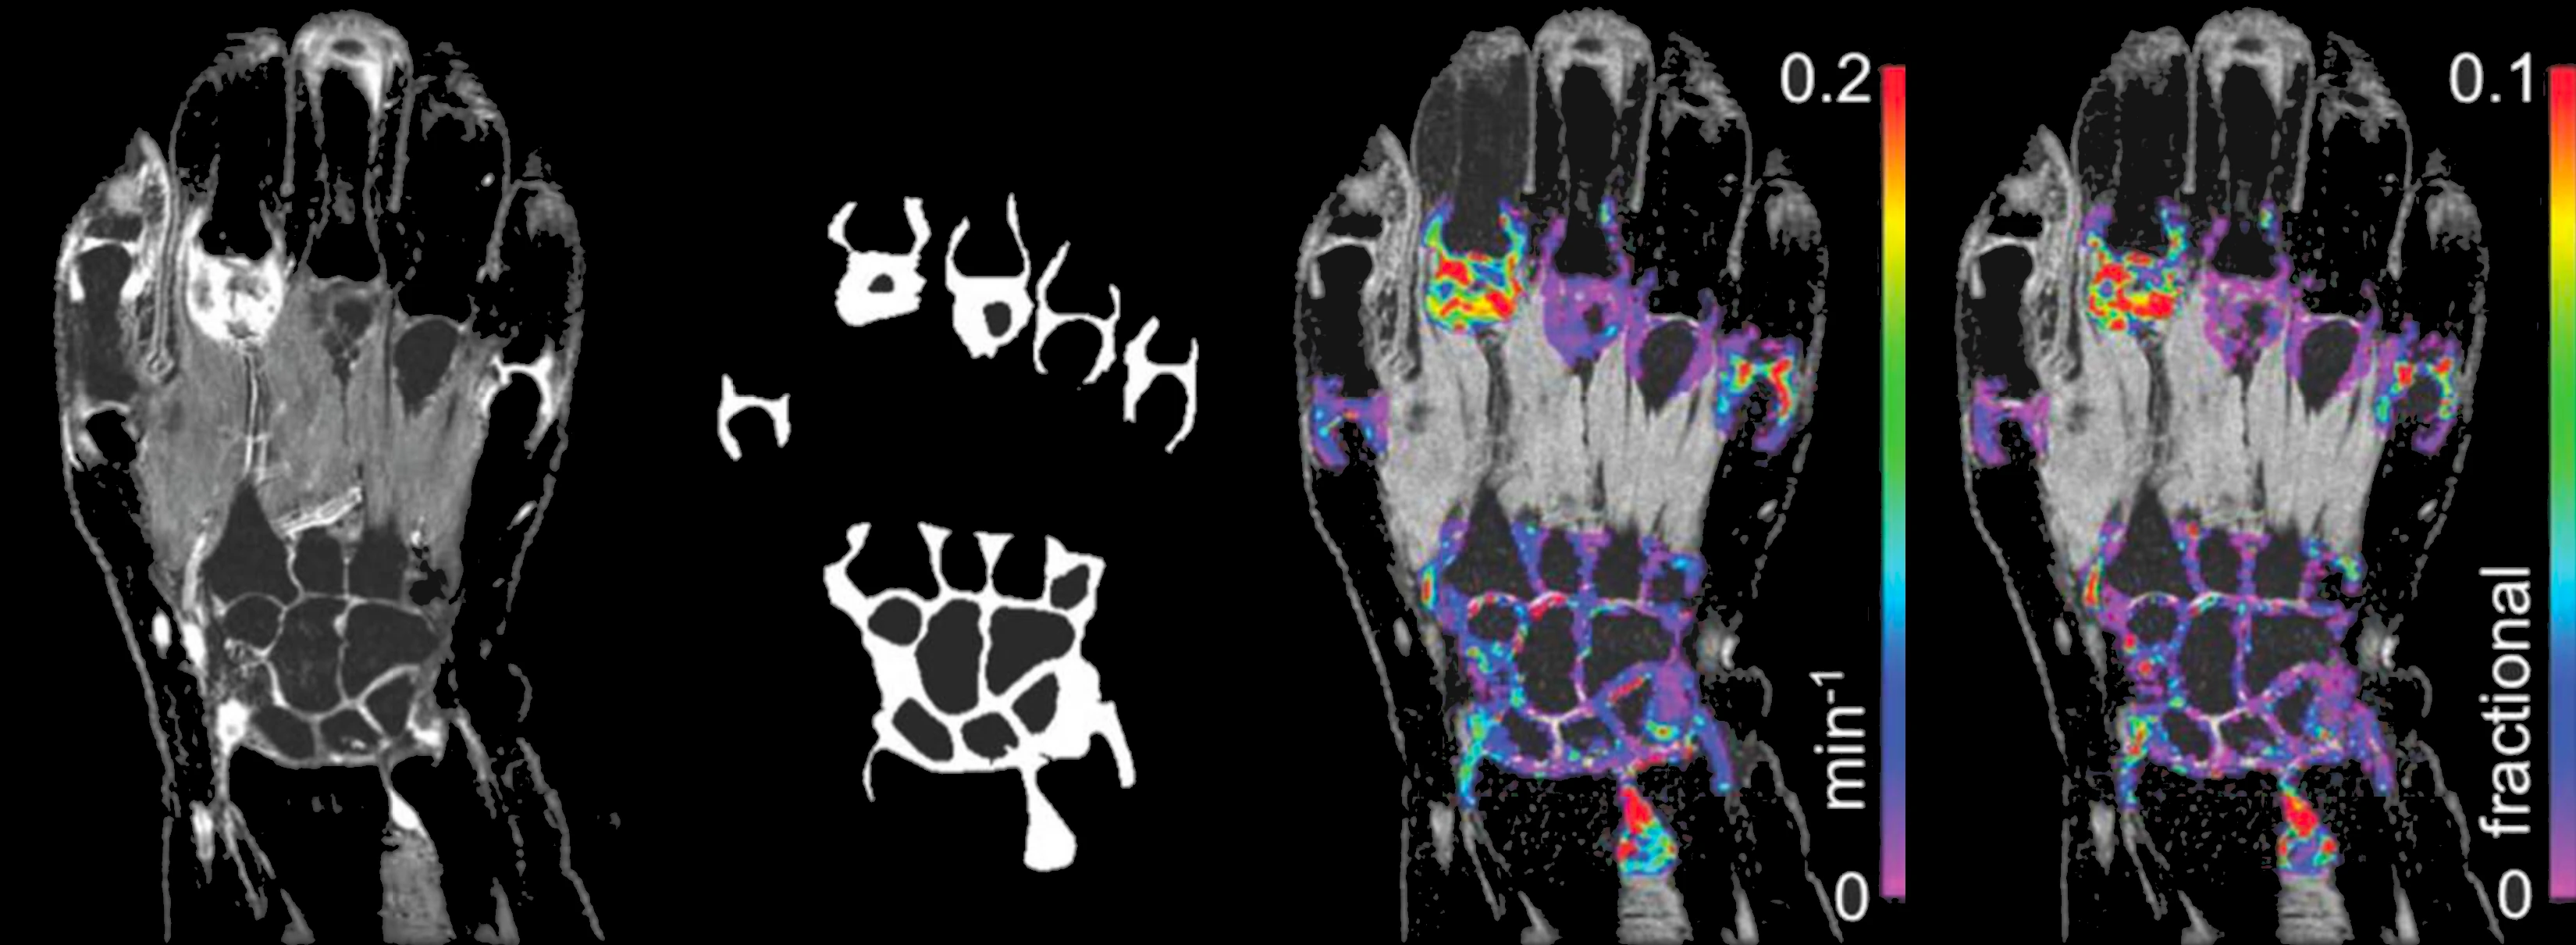

Inflammation

Inflammation biomarkers for arthritis, autoimmune disease, and organ injury.

- DCE-MRI Ktrans biomarkers of microvascular function

- Joint imaging in rheumatoid arthritis and osteoarthritis

- Renal imaging biomarkers including ASL, T1, T2, ADC

- Hypoxia and pH imaging methods (BOLD, OE-MRI, CEST)

- Sensitive, repeatable measurements with small cohorts